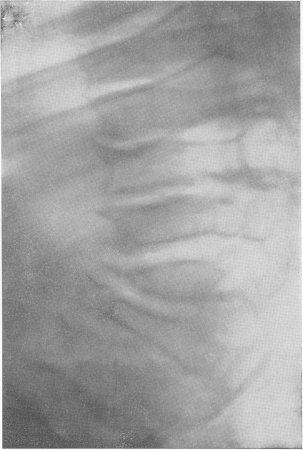

Fig. 280. Osteochondrodystrofia la un băiat de 7 ani. Imediat după naștere, arcul spate. Creștere scăzută, cu dificultate îndoire înainte. Explicați brusc brachypondylia sistemică.

Deformarea corpului uneia dintre vertebrele lombare superioare în proiecția laterală, extrem de tipică pentru osteochondrodystrofia și gargoilismul - angularea coloanei vertebrale. Tip de deformare conform Pfoundler-Hurler ("limbă inferioară"). Boala principală este complicată de rahitismul tratat cu succes; benzi de MS. Structura vertebrelor este defectuoasă, grosieră. Contururile corpurilor vertebrale sunt subliniate, dar pierd un curs neted, devin inegale. Cel mai caracteristic osteohondrodistrofii manifestare radiografice este definită, cu nimic pentru a se amestecă și diagnostically importante imagini deformare contur pe latura (fig. 281-283). Preocuparea este că una sau două vertebre, și anume, trecerea la lombare toracice - de obicei, I sau II la nivelul vertebrelor lombare, și vertebră toracică, uneori, XII, partea din față prezintă un defect. Jumătatea superioară a hipoplazica vertebrale, jumătatea inferioară se reliefează ca prova navei, și, prin urmare, în trepte din față a corpului coraco sau deformate, este nevoie de o conic, a subliniat forma anteriorly verhneperedny de circuit devine scara, terrasopodobnym.

Cocoșul cu constricția proceselor spinoase în regiunea lombar-toracică. Deformarea tipică a corpului vertebrelor toracice XII. Tip de deformare de către Morkio-Brailsford ("limba centrală"). Spondiloza secundară semnificativă secundară deformantă. Această așa-numitul prim tip tulpină - tip Pfaundlera-Hurler (M. Pfaundler, Gertrude Hurler), "limba de jos", de multe ori observat la gargoylizme (a se vedea mai jos.) (Figurile 281, 283, A.). In alte cazuri, corpul vertebral este întins scurtat și ascuțit în mijloc, la o distanță egală față superioară și inferioară zonelor, așa-numita tulpina tip doua - Morquio-Breylsfloda „limbă centrală“ (Fig 282, 283, B.). În unele cazuri, această caracteristică deosebit de calitativă de deformare a osteochondrodystrofei apare în organele nu ale unuia, ci mai multe vertebre adiacente. Această dimensiune redusă a vertebrelor nedevelopate, atunci când se alunecă din rândul drept înapoi, iar vertebrele toracice deasupra ei se atarna. Acesta este modul în care se dezvoltă deformarea coloanei vertebrale, kyfozei sau angulației, care este specifică osteochondrodystrofiei, adică îndoială unghiulară, o cocoșă. La distorsiune unghiulare foarte ascuțite se pot produce comprimarea suprafeței posterioare a corpului vertebrei deplasată a măduvei spinării, însoțite de consecințele neurologice corespunzătoare secundare severe, amenințătoare de viață. În craniu nu există nimic radiologic despre nimic. Se pare că este relativ mare. Zona șei turcești este normală. In cazurile severe, poate exista un anumit grad konveksobazii, coloana vertebrală împinge în sus de bază a craniului, care exacerbează în continuare scurtarea gâtului și apropierea craniului la cuștii toracice. Ar trebui, de asemenea, să acorde atenție cariilor dentare relativ frecvente dezvoltate.